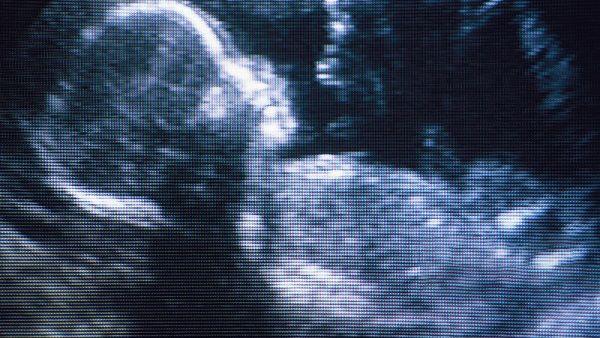

你这种情况是不能确定几次的,这个与人的体质有关,但你在这段时间还是很有必要观察胎儿打嗝的次数,一旦察觉到过多的话,建议你最好是去医院做b超检查,看一下孩子在母体子宫中的情况如何。

做B超能看到孩子在子宫内的发育情况

其实胎宝宝经常打嗝好不好还要看他在子宫内的发育情况怎么样,所以你在这段时间,要定期去医院做检查,观察孩子在子宫内的情况是否良好,同时,要多咨询医生在这期间,你需要注意些什么东西。